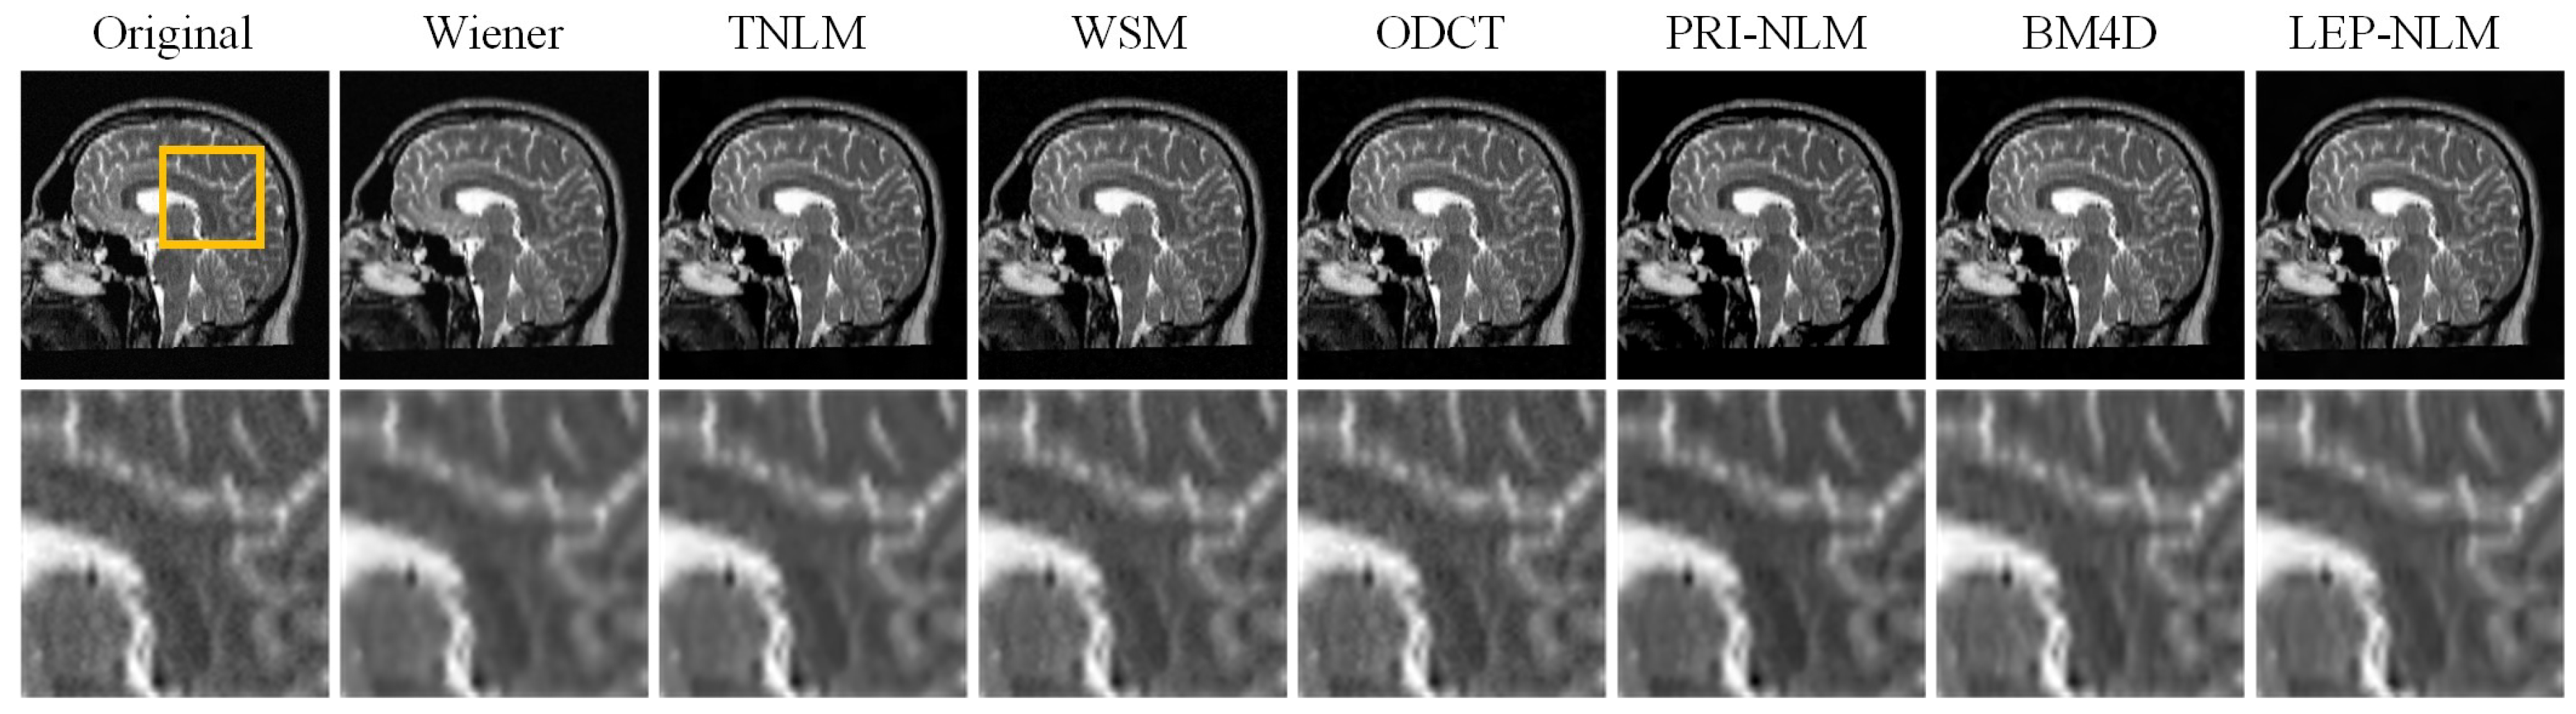

3.2. Real MR Images